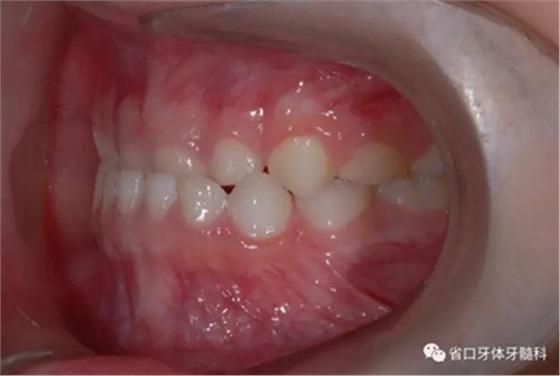

圖5 左側(cè)45度牙相